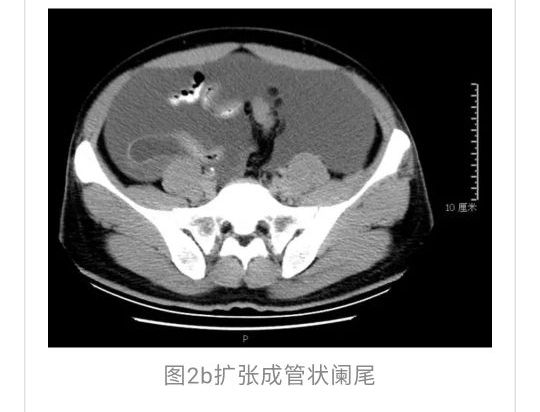

全腹CT:(1)结合病史考虑腹膜炎(见图2A),大量腹水;(2)右骼窝区管状样结构,考虑阑尾扩张(见图2B);(3)肝脏多发小囊肿(见图2C);(4)肝内胆管轻度扩张,建议隔期复查。

PET-CT检查:(1)腹盆腔大量积液,腹膜略厚,其间散在小淋巴结,代谢轻度增高,倾向腹膜炎可能性大,建议治疗后复查并密切复查肿瘤标志物;(2)双侧颈部领下、双侧腋窝淋巴略增大,代谢轻度增高,考虑炎性病变;(3)右肺下叶胸膜下钙化灶;(4)肝内多发囊肿,胆囊壁略毛糙;(5)右侧骼窝区细条形软组织影,代谢稍增高,考虑阑尾扩张。电子胃镜:(1)胃息肉(1枚己摘除);(2)反流性食管炎(A级);(3)慢性胃炎。电子肠镜未见结核、肿瘤性病变,未见阑尾开口扩张及周围组织红肿糜烂性病变,见图3。

与此同时,还应与肝硬化腹水、妇科肿瘤、肠梗阻等疾病相鉴别。此患者为男性,全腹CT及PET-CT均提示阑尾扩张,很大可能来源于阑尾黏液性肿瘤。阑尾黏性肿瘤早期可无任何症状,随着瘤体堵塞阑尾,累及浆膜下层,播散至腹盆腔,可形成大量的黏液性腹水,又称“胶腹”,则可出现腹痛、腹胀、腹围增加等症状。通过本病例分析认为此类患者,腹穿时若发现腹水不易抽出或抽出物为黏稠胶冻样,腹部B超提示液性暗区内有漂浮的团状回声有分隔,撞击腹部后可出现“礼花”样改变,肝脾包膜完整不光滑,有弧形压迹,全腹部CT示弥散占位,可见mantle和scallping征、大网膜成饼状且阑尾扩张应高度怀疑本病。